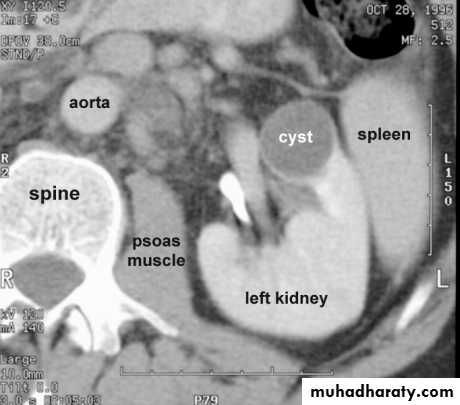

SIMPLE RENAL CYST* Common cause of renal mass .

* Uncommon under age of 30 years , most common over 50 years .

* Single or multiple .

* Usually cortical in origin .

* Varies in size ; few mm to 25 cm .

* Contains straw color fluid , with thin fibrous wall lines by flat epithelium .

* Clinically silent , large cyst can shows palpable mass .

* Calcification is rare , normal renal function .

IVU :-* Nephrogram shows filling defect .

*Displacement , elongation & stretching of PCS which depend on size and site of the cyst .

US :-

shows echo-free cystic lesion with posterior enhancement.